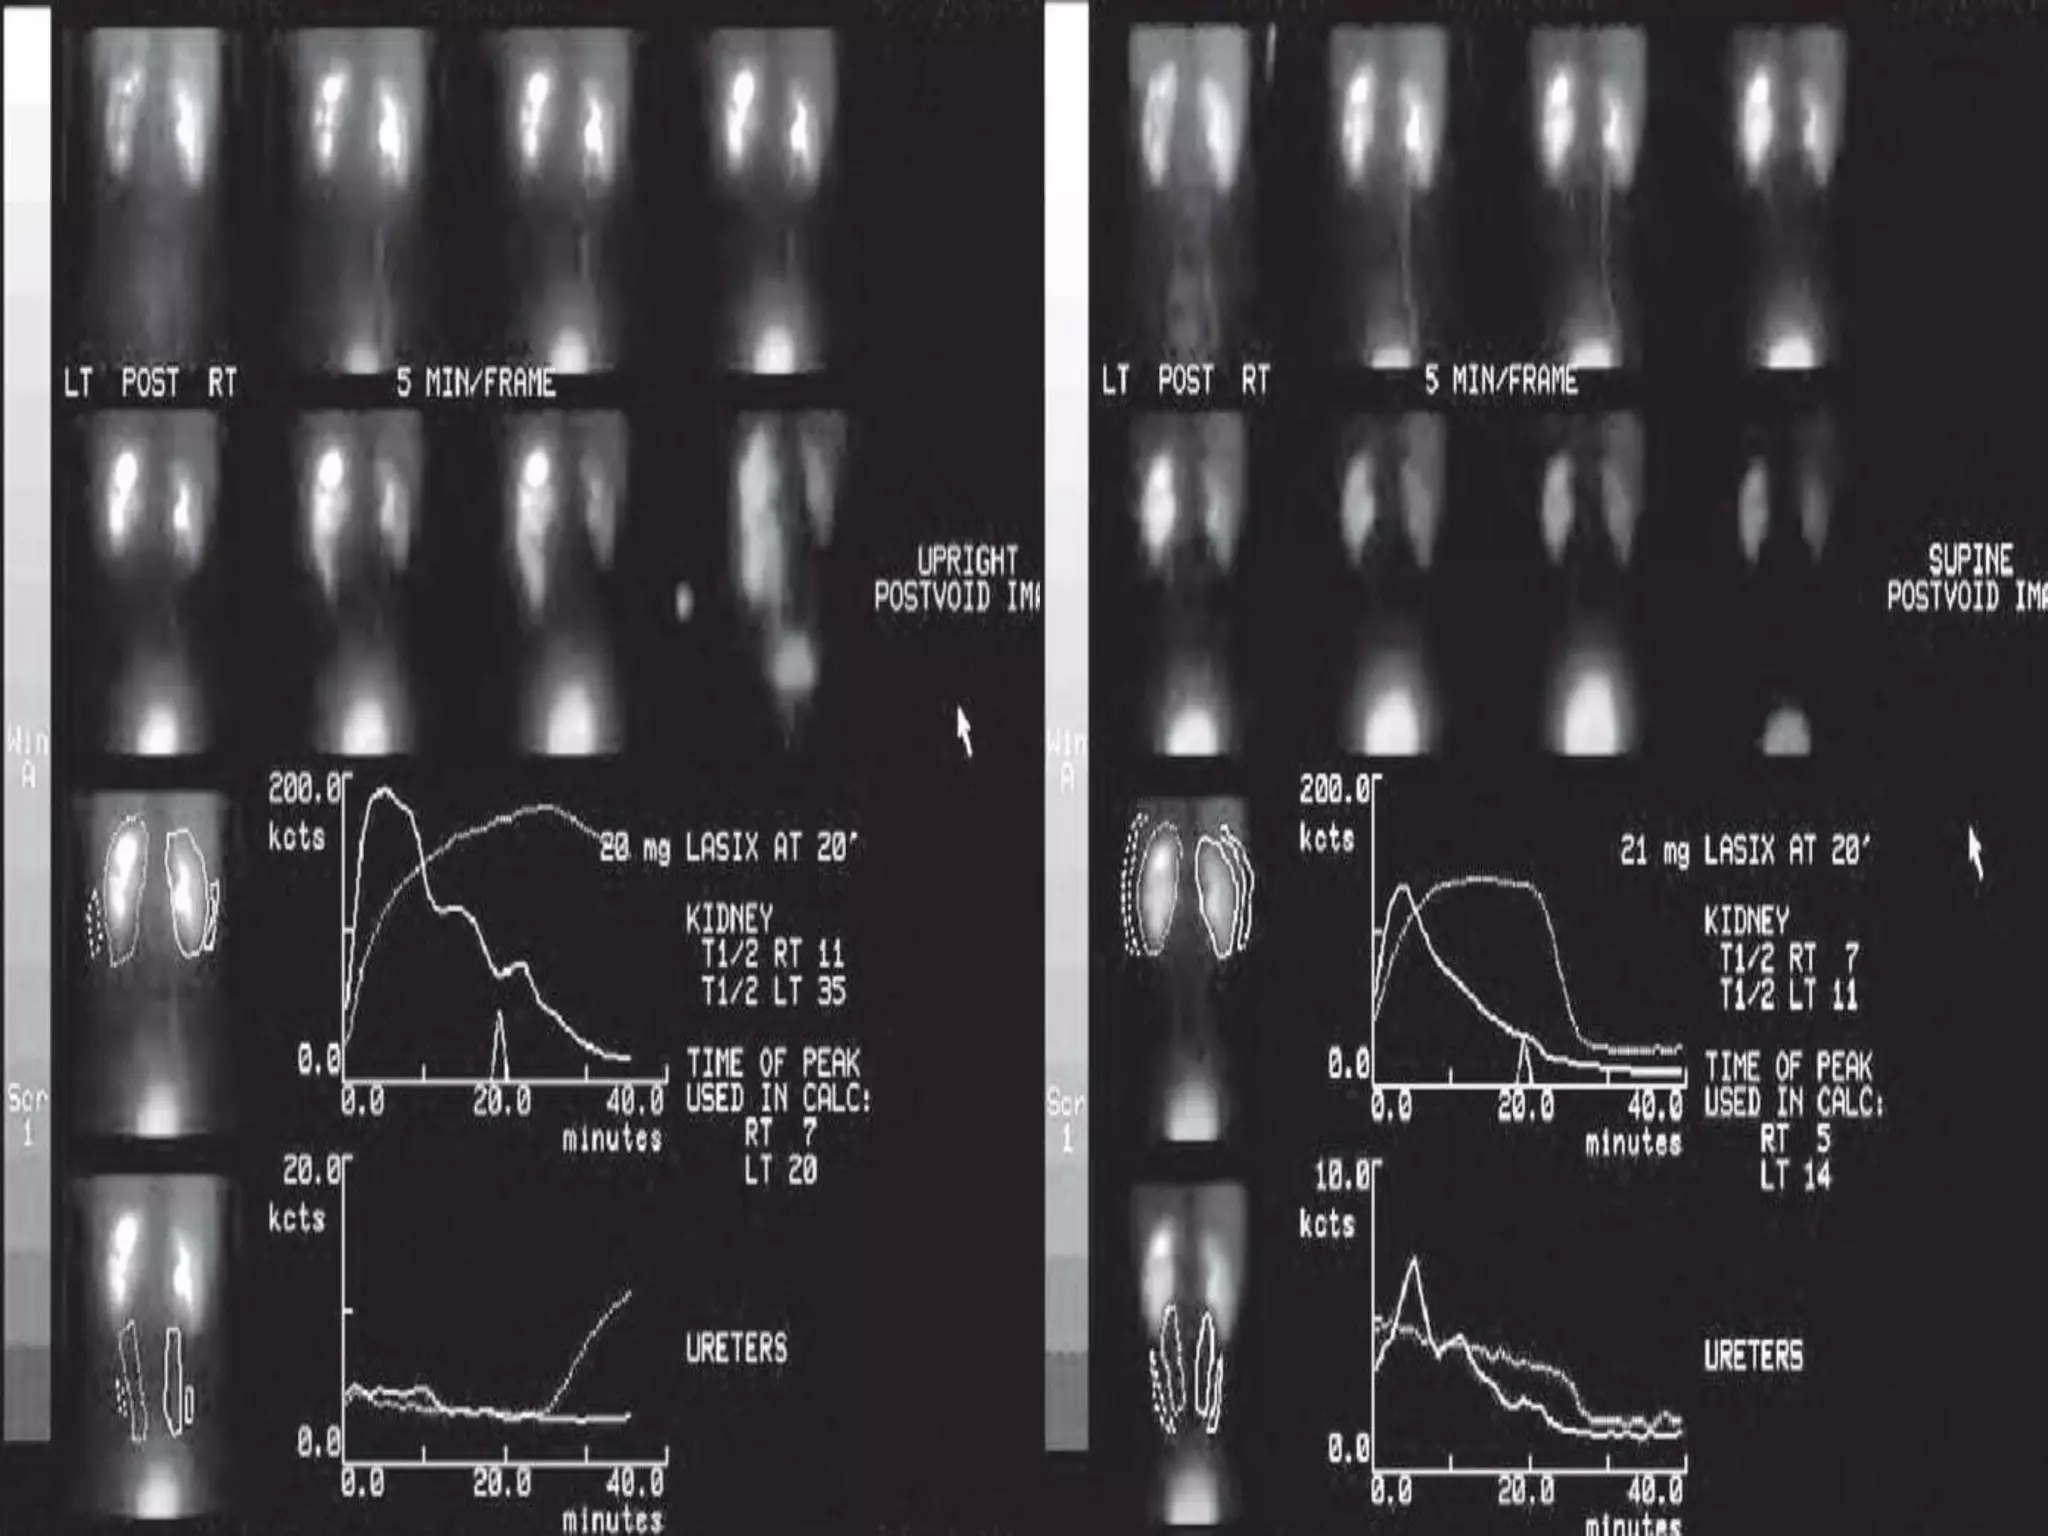

DIURETIC RENOGRAPHY

• It (renal scan and the administration of a

diuretic) is used to diagnose urinary tract

obstruction.

• It measures the drainage time from the renal

pelvis (referred to as washout) and assesses

total and each individual kidney's renal

function.

•The washout measurement correlates with the

degree of obstruction.

In general, a half-life greater than 20 minutes to

clear the isotope from the kidney is

considered indicative of obstruction.

99MTC-MAG3

-It provides quantitative data regarding

differential renal function and obstruction,

even in hydronephrotic renal units.

-There is evidence that the diuretic

renography using MAG-3 is a most accurate

study for patients with UPJ obstruction

following therapeutic intervention